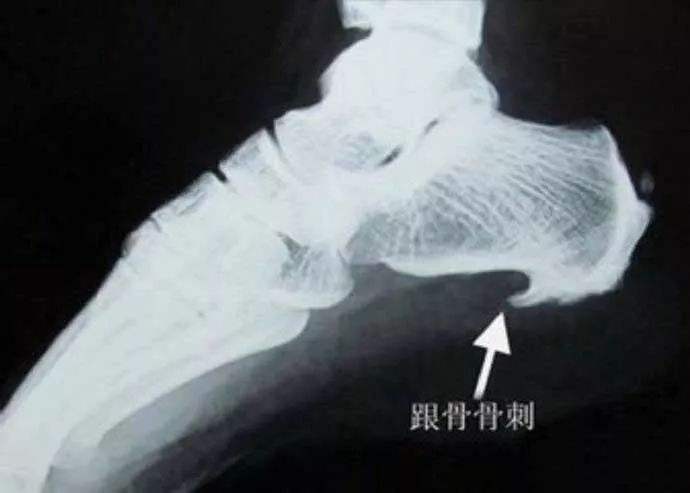

说了这么多足跟痛,重回主题,再谈跟骨骨刺,在足跟痛的患者中,很多人都有足跟骨刺的存在,那骨刺到底会不会引起足跟痛呢?我的回答是,一部分人的跟骨刺,是可以引起足跟痛的,但仅仅是一部分而已!

曾经有人做过调查,大约30%的人从三十岁开始就会出现跟骨骨刺,随着年龄的增长,跟骨骨刺的检出率逐年提高,到七十岁时,跟骨骨刺的检出率就几乎百分之百了,但事实上,七十岁的人并不是百分百出现足跟痛,真正跟骨骨刺引起的疼痛只是很少的一部分人群而已。从X片上,大家可以观察到,几乎所有的跟骨骨刺都是尖端向前的,为什么会出现这种情况呢?这就要谈到足跟骨刺的产生机理了!

针刀创始人朱汉章教授是最早否认骨质增生退变学说的专家之一了,他把骨质增生的原因归责于三种力,压应力、涨应力和拉应力,而跟骨骨刺就是“拉出来的”,前面说过,足底肌腱就像一根弹簧,维持着足弓的稳定,而足跟骨前侧是拉应力最集中的地方,随着足底韧带的反复牵拉,难免会在跟骨附着点处出现韧带损伤,人体为了修复这种损伤,就会调集大量的钙离子沉积在足底韧带跟骨附着点处,久而久之,就形成了尖端向前的跟骨骨刺,所以说,跟骨骨刺只不过是人体的一种自我修复、加强防御罢了,极少数人群修复过程中,会造成对穿行其中的末梢神经的卡压,或伴有不同程度的无菌性炎症,而出现足跟痛,这种足跟痛是最好解决的,我们只需要一枚小针刀,在骨刺尖端切断几根紧张的韧带纤维,卸掉过大的拉应力,足跟疼痛就会立马消失!值得一提的是,很多跖筋膜炎、跟骨脂肪垫炎、跟骨骨刺的引起的疼痛都是并存的,如果按疼痛部位详加区分,跖筋膜炎多位于跟骨前内侧,脂肪垫炎多位于跟骨正中,跟骨骨刺多位于跟骨正前方位置!在笔者写这篇文章的时候,正好有一对老夫妻都是因为足跟痛来诊,笔者就几种临床常见证型做了简单分析,同时录制视频一篇,感兴趣的亲们可以关注下!